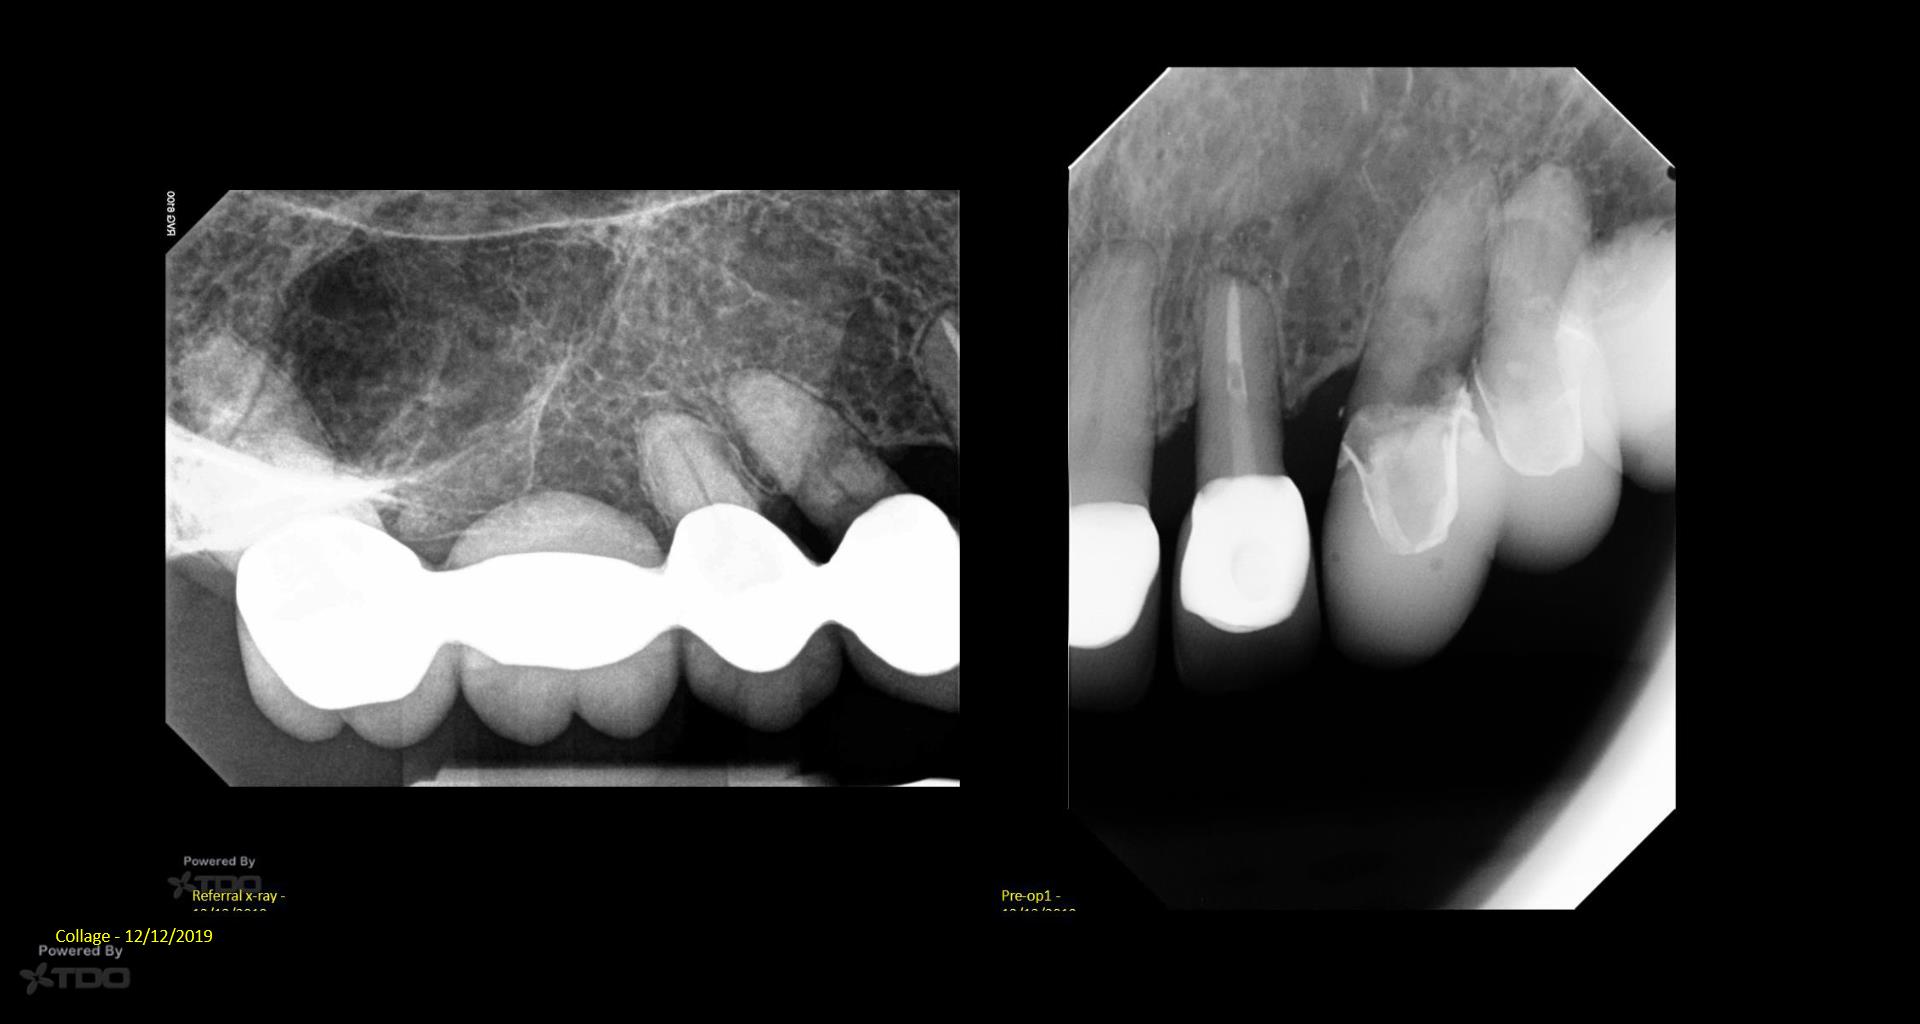

I posted this last month after the consult. There was mixed TDO advice—some said “do it” and others said monitor. Reluctantly, I did it Monday. I couldn’t really address the ECIR that was sub-osseous without removing way too much bone. I just hit it with the Pear Diamond as well as I could. Time will tell if it was a fool’s errand. I video’d the whole thing but don’t have the time to edit it. gbc